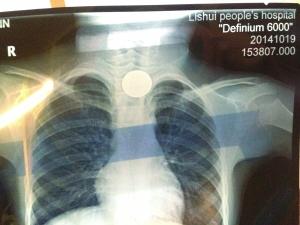

卡在食道的硬币。金陵晚报记者 徐赟 摄

昨天下午3点多,家住溧水的六岁男孩张亮(化名)在与同伴玩耍时把一枚一元硬币含在了口中,没想到哈哈一笑时,他将一元硬币吞了下去,随即张亮被从镇上转到溧水医院后又转移到儿童医院,医院确认幸好硬币停留在食道中,并无生命危险。

昨天下午4点半,父母抱着孩子焦急地来到了儿童医院的抢救室,记者在抢救室里看到,此时的张亮情绪比较稳定,父亲称孩子现在基本上不能说话,“好在在溧水医院拍片之后,医生已经确认硬币在食道内,并没有进入气管的危险。”